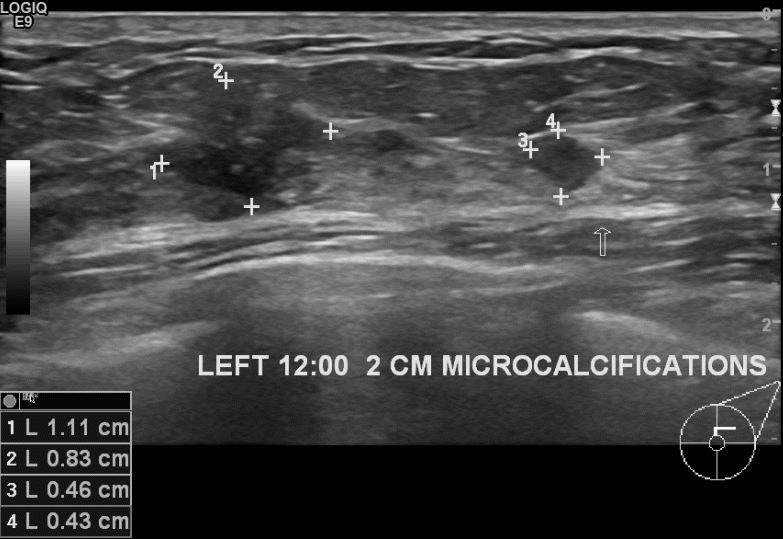

상기환자 40세 여자환자분으로 1년전 단유후 유두소양증 있어 검진받아본후 멍울발견되어 좌측유방 12시방향으로 중심핵생검 실시하여 상피내암진단되셨습니다.